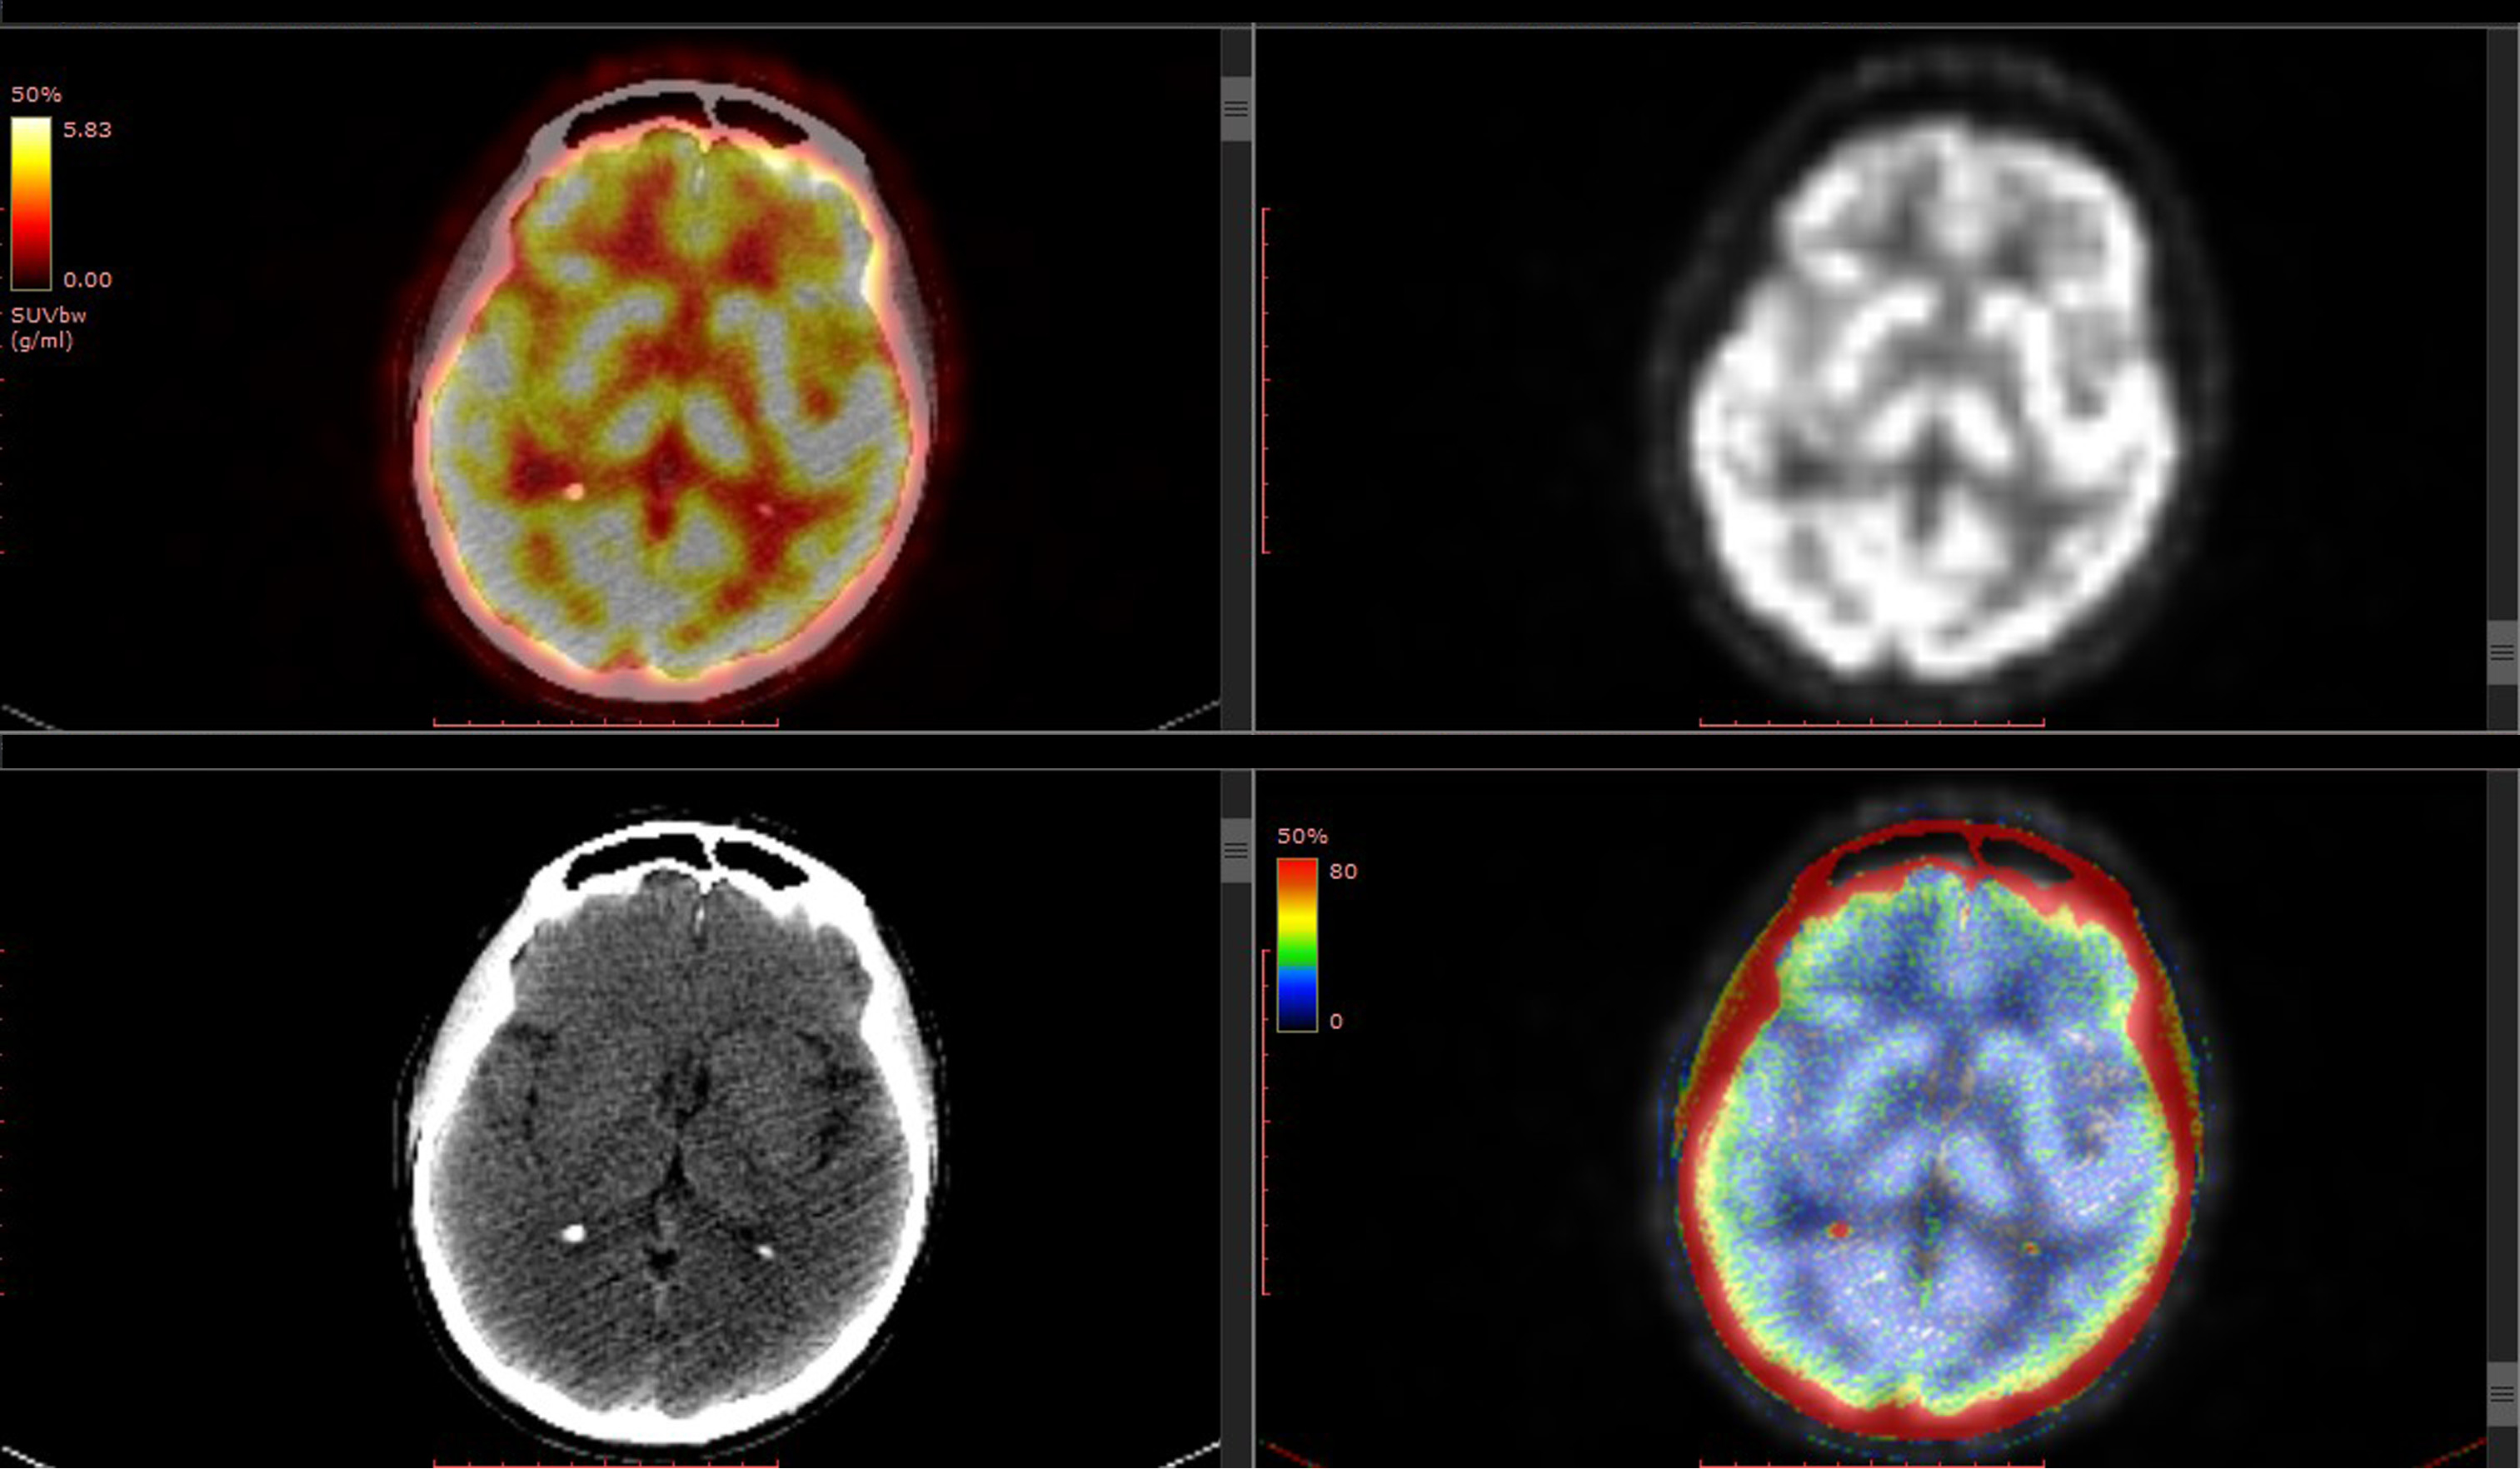

国内外神经外科专家提醒,日常生活中当出现以上脑肿瘤相关症状应及时到医院就诊,可以进行相关的化验或检查,例如鞍区病变会引起激素的改变,可以抽血化验垂体功能。而其他颅脑肿瘤由于缺少特异性的化验指标,抽血和常规体检难以发现隐藏的病变,则应该选择相关的检查如颅脑部CT或MRI。

如果患者有其他部位的肿瘤病史,则建议每年到医院复查,同时建议做颅脑部的影像学检查。因为约有15%~30%的肿瘤患者会发生颅内转移并产生相应的症状。如小细胞肺癌生存期超过两年的患者,脑转移率高达80%。

一旦发生脑转移,患者的生活质量会受到较大的影响,生命也被严重威胁。对于容易发生脑转移的肿瘤患者而言,较好在每年复诊化验相关肿瘤指标的同时做一次颅脑的MRI。以便及早发现颅脑转移,及时治疗。